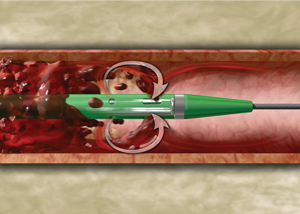

O Sistema de Trombectomia AngioJet é um dispositivo de trombectomia periférico farmacomecânico com aspiração ativa e liberação lítica Power Pulse™ projetado para tratar a gama mais ampla de vasos com trombose, restaurando rapidamente o fluxo sanguíneo.

O Sistema de Trombectomia AngioJet é um dispositivo de trombectomia periférico farmacomecânico com aspiração ativa e liberação lítica Power Pulse™ projetado para tratar a gama mais ampla de vasos com trombose, restaurando rapidamente o fluxo sanguíneo.

O sistema de Trombectomia AngioJet proporciona a potência e flexibilidade para remoção rápida de trombos, restauração rápida de fluxo sanguíneo, melhora de sintomas e facilidade de uso.

Aspiração ativa e entrega lítica Power Pulse para coágulos resistentes.

O Sistema de Trombectomia AngioJet permite a remoção percutânea de trombos

localizadas em artérias e veias periféricas, pontes de safena, artérias coronárias e condutos de acesso AV nativos ou sintéticos. A trombectomia é realizado com jatos de solução salina de alta pressão contidos na haste do cateter. O jatos de solução salina criam um efeito de baixa pressão para atrair o trombo para o cateter, fragmentar

o trombo e remova o trombo do local de tratamento. O sistema consiste de um conjunto de trombectomia de uso único (vários modelos disponíveis) e um consola móvel.

Mecanismo de Ação

1. O Console AngioJEt monitora e controla o sistema.

2. O Console energiza a bomba, que envia solução fisiológica pressurizada para a ponta do cateter.

3. Os jatos de solução fisiológica viajam para trás para criar uma zona de baixa pressão causando um efeito de vácuo. (Imagem 1)